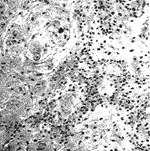

从上述时间表可以清楚地看出:将超声处理方法应用于快速切片中,可稳定地缩短组织处理时间,提高制片效率;同时根据质量观察,运用该方法制取的切片,组织收缩少,脆性小,切片薄而完整,染色特别鲜艳明丽,层次清晰,为提高镜检的准确性创造了条件;另外,组织蜡块和切片均能长期保存,不易褪色,有利于教学、科研和学术交流,完全符合优质病理切片的质量要求(见附图)。

舌分化性鳞癌 HE×100

交感神经节 HE×100

附图 快速切片质量观察